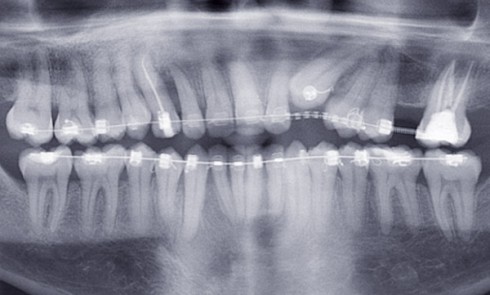

Article réservé à nos abonnés Démarche diagnostique clinique et radiologique face à une dent incluse

L’inclusion dentaire est définie comme une « dent retenue dans l’arcade maxillaire ou mandibulaire au-delà de la date d’éruption, entourée de...